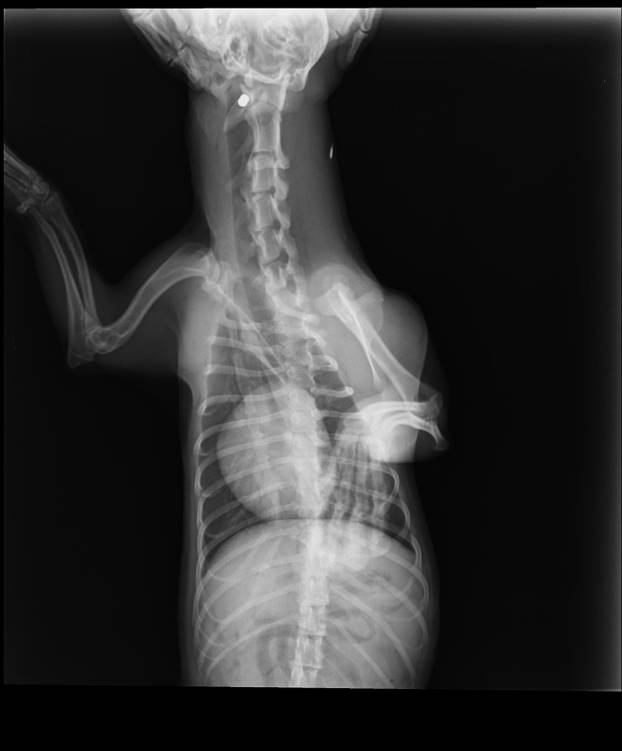

Metak je visoko gore i duboko kod kralješka. Zbog izazivanja većih lezija odustalo se od vađenja metka - stoji u nalazu kujice Lene

- Sinoć tijekom šetnje pas se trznuo, a kada su došli kući vidjeli su krv iz vrata. Bili su u stanici Pakrac i tamo su obradili ranu. Metak je veličine dijabole 6,10 - 5,16 mm. Metak je visoko gore i duboko kod kralješka. Zbog izazivanja većih lezija odustalo se od vađenja metka - stoji u nalazu kujice Lene.